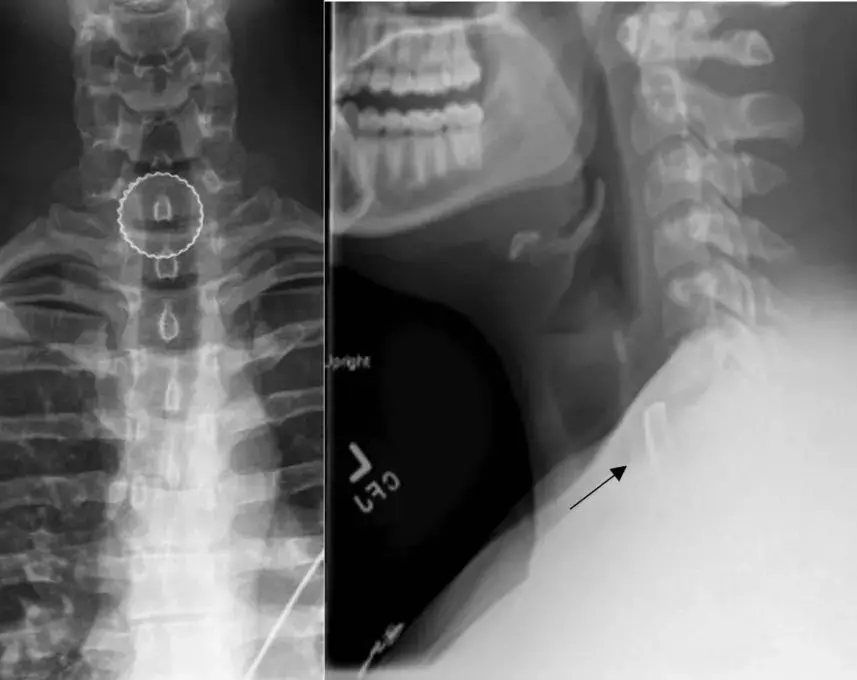

美國一名19歲男子與朋友飲酒玩投杯球(beer pong)時,意外將掉入塑膠杯的啤酒瓶蓋連同啤酒一併吞下,事隔約一小時才因喉嚨劇痛、吞嚥困難及呼吸異常而送院,X光檢查發現瓶蓋卡在食道。

雖然男子的呼吸道未完全阻塞,但醫生擔心瓶蓋可能導致器官穿孔或組織壞死,遂決定進行緊急手術。醫療團隊利用內視鏡經口腔伸入食道,成功將瓶蓋取出,男子術後並無後遺症。